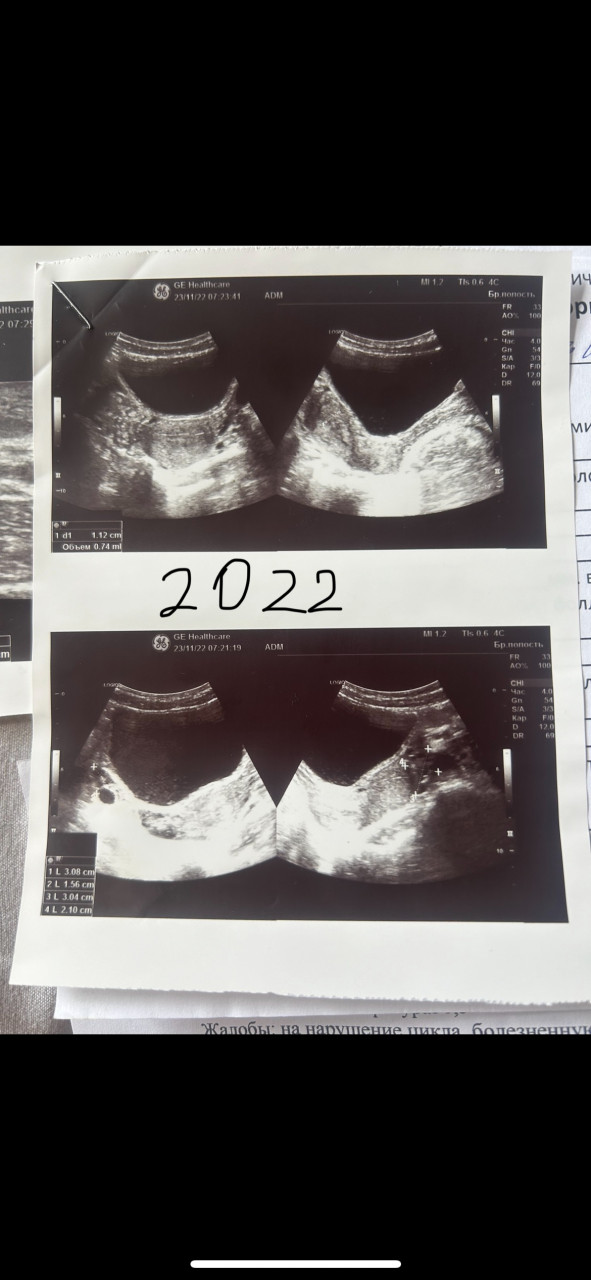

Здравствуйте, подскажите пожалуйста по моему вопросу. У меня очень болезненная менструация очень много крови со сгустками выходит цикл нерегулярный лет с 15 ходили по врачам делали узи ставили диагноз вторичная олигоменорея и вторичная дисменорея назначали циклодинон от которого толку 0 от боли так тоже ничего и не помогает назначали и пить до менструации обезболивающее за 5 дней до найз по 1 таб 2 раза в день и 3 дня менструаций, в первый особенно болезненный день свечи с индометацином больно невозможно как схватки потом в 17 лет поставили диагноз диффузно кистозная мастопатия в груди ощущаю комки грудь очень болит до месячных и во время них опять же назначали мастодинон который ничего не дал и обезболивающее вот и все пропила мастодинон 3 мес. В больнице врач узи начала говорить а кто вам такое в груди увидел хотя это она же и делала узи в первый раз я прикреплю ниже узи малого таза за 2021 и 2022 год давно подозревала у себя эндометриоз все симптомы подходят и вот вчера мама поехала на узи из-за кровотечения и ей поставили эндометриоз впервые за 40 лет в другой клинике заключение: Эхографические признаки гиперплазии эндометрия, умеренных диффузных изменений миометрия по типу эндометриоза, миомы тела матки небольших размеров, фолликулярной кисты правого яичника.  зашла сегодня ради интереса в чат джи пи ти и отправила ему свое узи он расшифровал мне его абсолютно по-другому за 2021 год вообще сказал что это узи мочевого пузыря я вообще в шоке а в узи за 2022 год нашлись действительно болезни а врач узи пишет что там все в норме кому верить уже не знаю( забыла указать длина цикла 32-51день, менструация длится 10 дней под конец совсем мазня и раньше бывало такое что между месячными была мазня в середине цикла сейчас во время овуляции болит левый яичник во время менструации боль отдает аж в ноги они будто отнимаются

Заключение в чат джи пи ти узи за 2022 год Предварительное заключение (не заменяет очную консультацию): УЗИ-признаки:Множественные фолликулярные структуры в левом яичнике, самая крупная — до 3,08 см.Возможно наличие функциональной (овуляторной) кисты.Правый яичник без выраженной патологии, небольшое жидкостное образование.

Заключение УЗИ 2021 матка 40*28*46 мм эндометрий 5мм, однородный, миометрий не изменен, левый яичник 30*19*20, фолликулы до 5 мм в поле зрения 8-9 шт, правый яичник 28*16*17мм фолликулы до 7 мм, в поле зрения 7-8 шт. В дуглассовом пространстве жидкость -. УЗИ 2022 матка 41*30*48 мм, эндометрий 11мм, однородный, полость матки не расширена, миометрий однородный, шейка матки без особенностей, правый яичник 30*15*18 фолликулы до 13 мм в диаметре, 7-8 шт в поле зрения левый яичник 30*21*20 мм фолликулы до 6 мм в диаметре, 9-10 штук в поле зрения в дугласовом пространстве жидкость в небольшом количестве 5 мл.